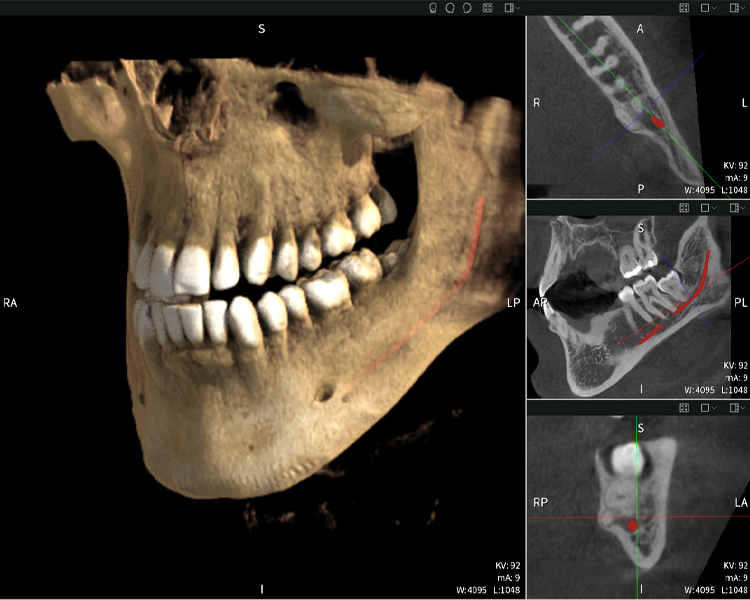

Figura d: Resultados de imagen de Seethrough Max, sobre un fondo negro.

Figura d

Las figuras b–d muestran varias vistas de una reconstrucción 3D de la mandíbula, proporcionando una visión general completa de la anatomía mandibular, la posición de los nervios en relación con los dientes y permitiendo evaluar la simetría y alineación dentaria.

La figura d muestra el diente 48 previamente tratado, con la corona retirada y las raíces dejadas en proximidad al nervio, lo que ilustra el alto riesgo de daño nervioso.